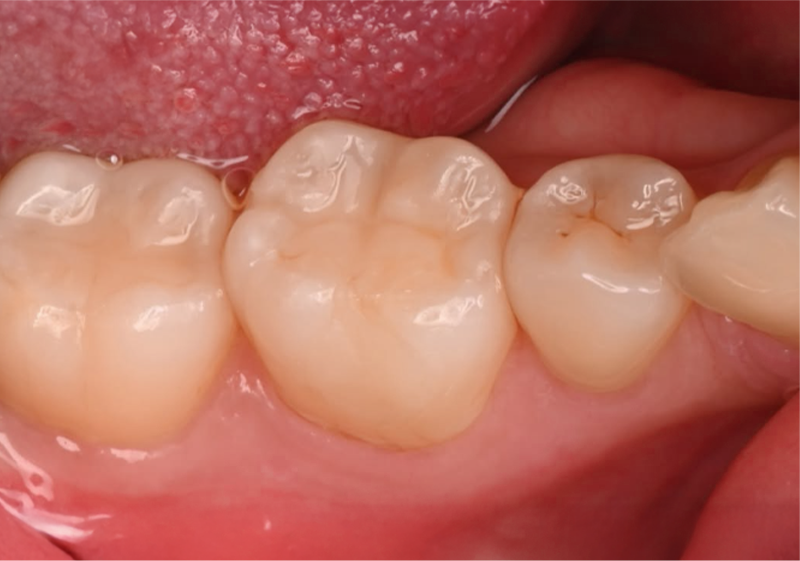

레진빌드업은 치과의사가 구강 내에서

직접 치아의 형태를 세심하게 만들어나가는 수복 방식입니다.

자연치아의 구조를 모방(biomimetic) 하여

신중하게 접착하는 과정을 거치며,

본래 치아와 조화롭게 기능할 수 있도록 돕습니다.